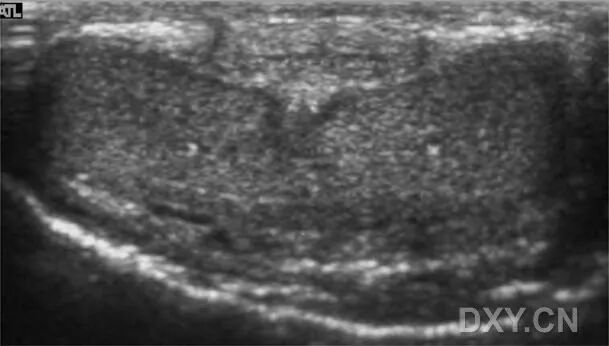

B 海绵体注射后的前几分钟阴茎海绵体中心部分的海绵体窦开始扩张,表现为比外周部分的回声低。

阴茎海绵体的回声表现为进行性减低,肿胀时从阴茎海绵体动脉周围开始,原因是海绵体窦的扩张。